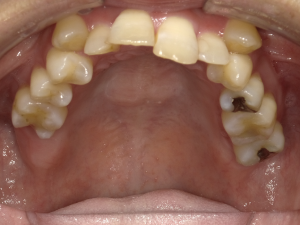

60代 男性 インプラント治療

| 年代・性別 | 60代・男性 |

| 主訴 | 健全な歯に負担をかけない治療をしたい。 |

| 部位 | 右上1左上1 |

| 治療期間 | 約1年3ヶ月 |

| 費用 | ¥686,000(税込) |